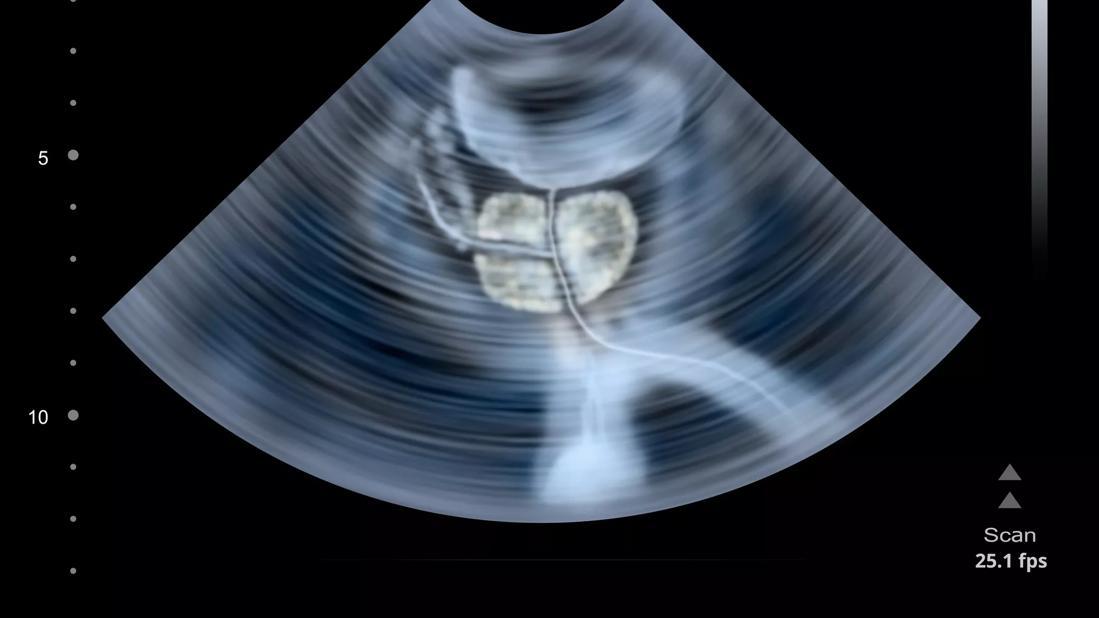

High-intensity sound waves target the tumor through an ultrasound probe inserted into the rectum. The surgeon controls the probe with a robotic arm that moves in millimeters.